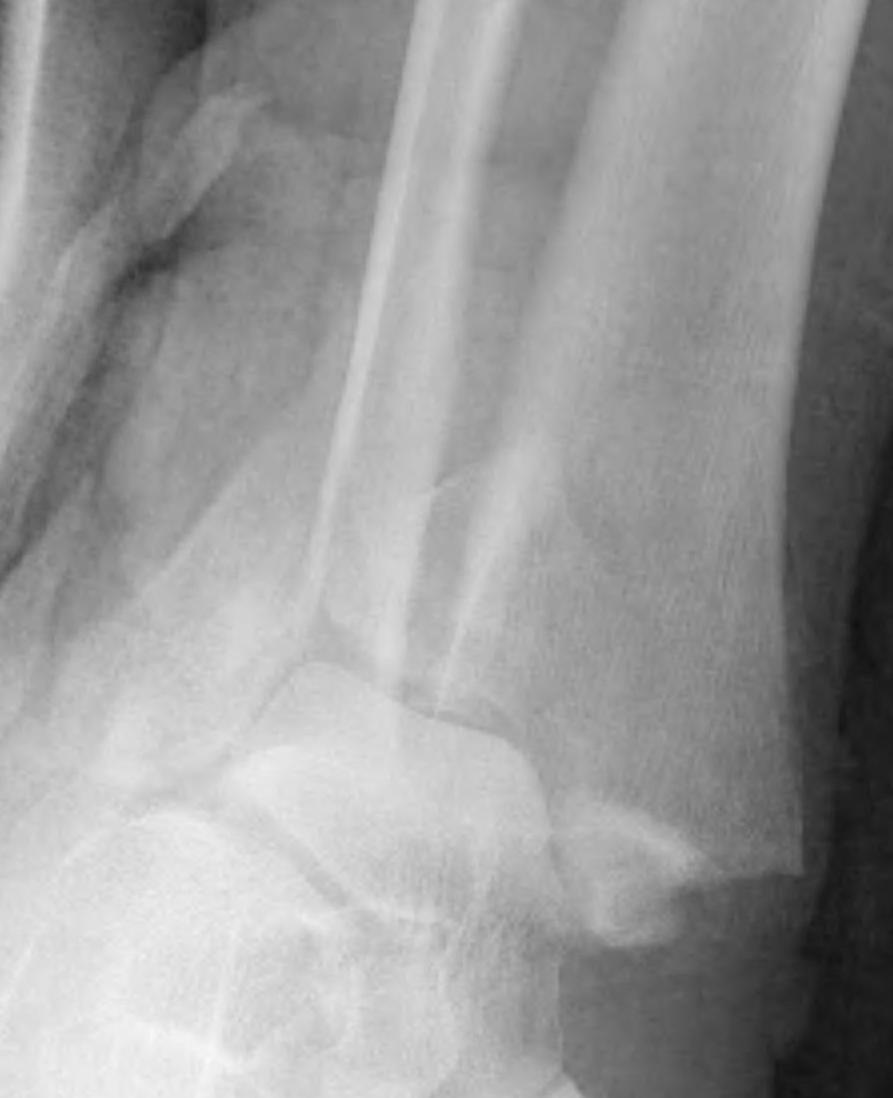

Lateral talar shift / increased medial clear space / deltoid ligament injury

Ankle Fracture Increased Medial Clear SpaceAnkle Fracture Increased Medial Clear Space 2Maisonnerve

Tibia / fibular overlap < 1mm / syndesmotic injury

Ankle Fracture Syndesmosis WidenedAnkle Diastasis